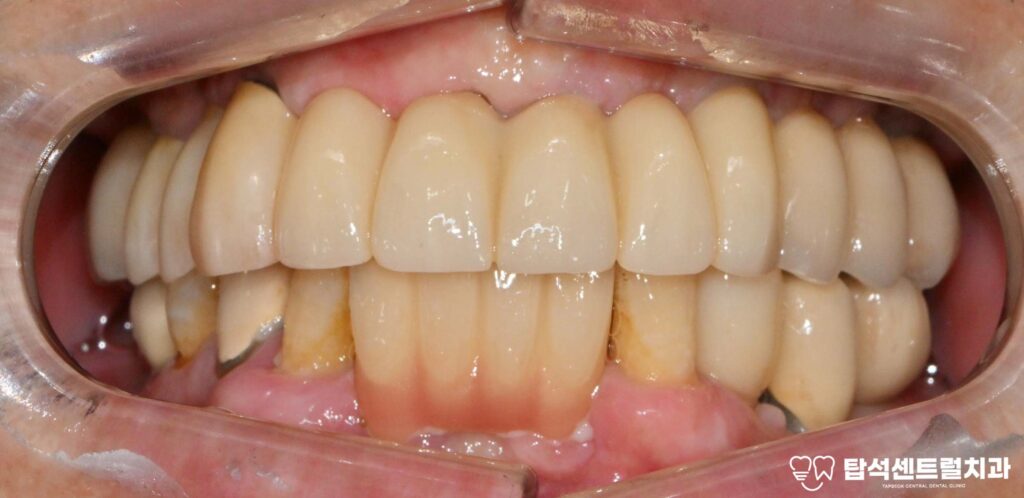

다행히, 왼쪽 위턱의 송곳니는 상태가 양호하여

임플란트 한개 제거 후 장기적인 안정성을

위해 앞니에 2개의 임플란트 를

추가 식립한 모습입니다.

이때, 결손되어 비어 있었던

아래 작은 어금니쪽에도

임플란트 하나를 같이 심어주었습니다.